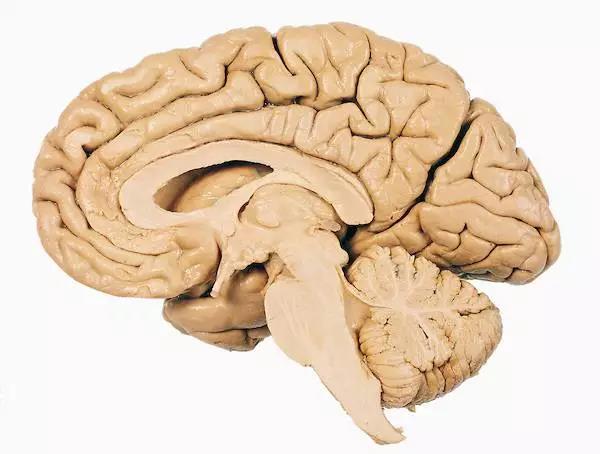

讓我們使用半球橫截面看看大腦的主要部分。因此,這是你腦袋里大腦的樣子:

現在,讓我們把大腦取出來,并刪除左半球,這讓我們能看清楚內部。

神經學家 Paul MacLean 做了一個簡單的示意圖,說明我們前面談到的爬行動物大腦在進化中的第一次出現,然后是在哺乳動物興盛階段形成的古生哺乳動物腦和新哺乳動物腦。

也可以這么表示

讓我們來看看每個部分:

讓我們使用半球橫截面看看大腦的主要部分。因此,這是你腦袋里大腦的樣子:

現在,讓我們把大腦取出來,并刪除左半球,這讓我們能看清楚內部。

神經學家 Paul MacLean 做了一個簡單的示意圖,說明我們前面談到的爬行動物大腦在進化中的第一次出現,然后是在哺乳動物興盛階段形成的古生哺乳動物腦和新哺乳動物腦。

也可以這么表示

讓我們來看看每個部分: